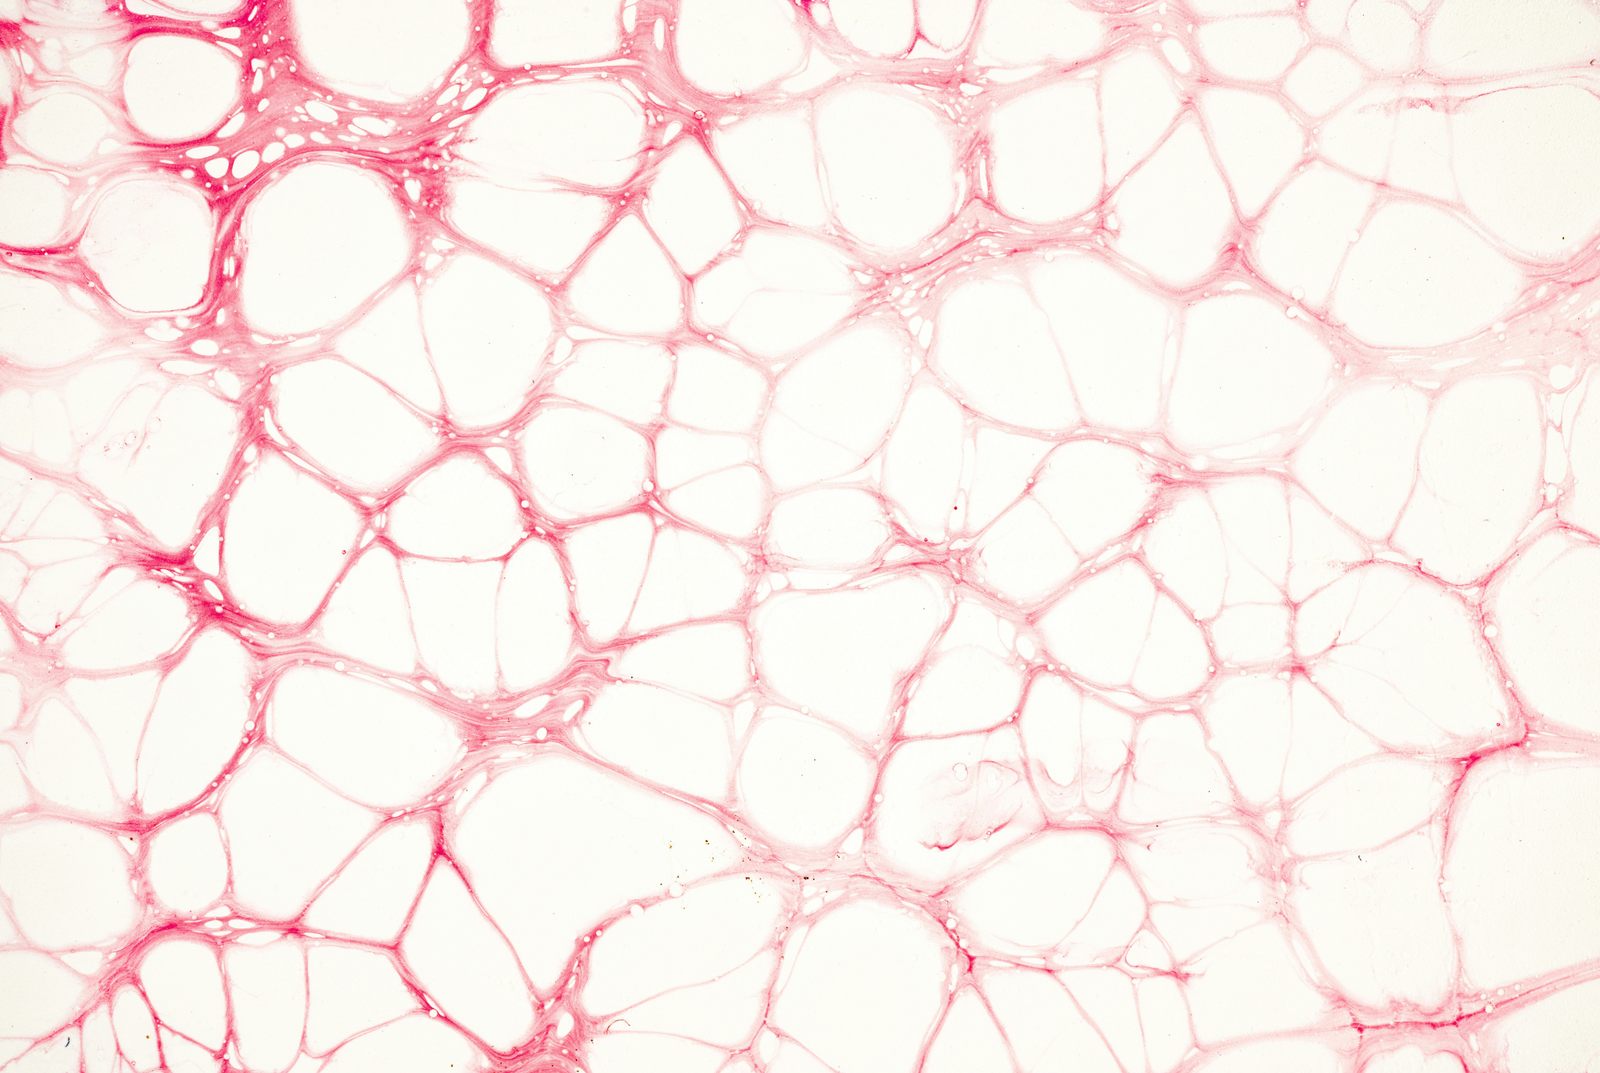

Zombie cells (cellular senescence)

Some cells stop dividing but don’t die. These “zombie cells” release toxins that damage nearby healthy cells. Over time, cell senescence leads to tissue aging, inflammation, and higher risk of chronic diseases like heart disease and Alzheimer’s disease.